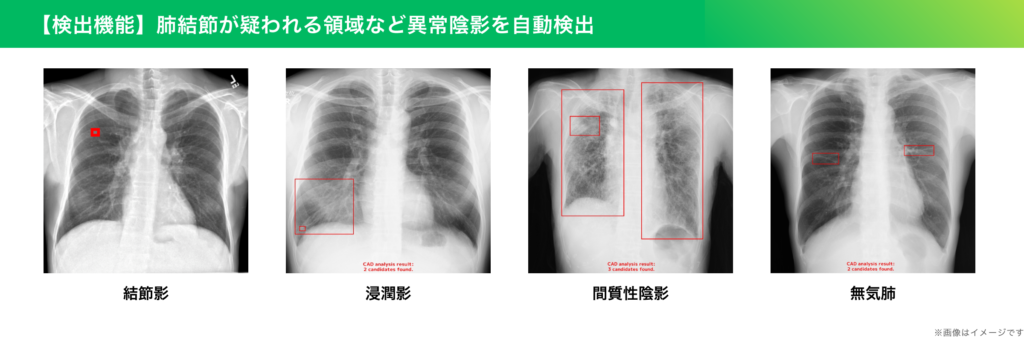

画像診断支援AIとは、レントゲン、CT、MRIなどの医療画像をAI(人工知能)が解析し、病気の兆候や異常な部分を自動的に見つける技術です。AIは、過去に撮影された大量の医療画像を学習しており、画像を解析して「ここに異常があるかもしれない」と判断します。

このAIはあくまで医師を「支援」するものであり、最終的な診断や治療方針の決定は医師が行います。当院では胸部レントゲンのAI診断を導入し、人間の目だけでは見逃してしまう可能性のある小さな病変もAIが指摘することで、より正確な診断につながるよう精度を高めていきます。

胸部単純写真において、肺がんを疑う所見などをAIが的確に検出します。もし疑わしい所見があった場合には、そのまま当院で胸部CTなどによる精密検査を行い、真の異常かどうかを判断することができます。